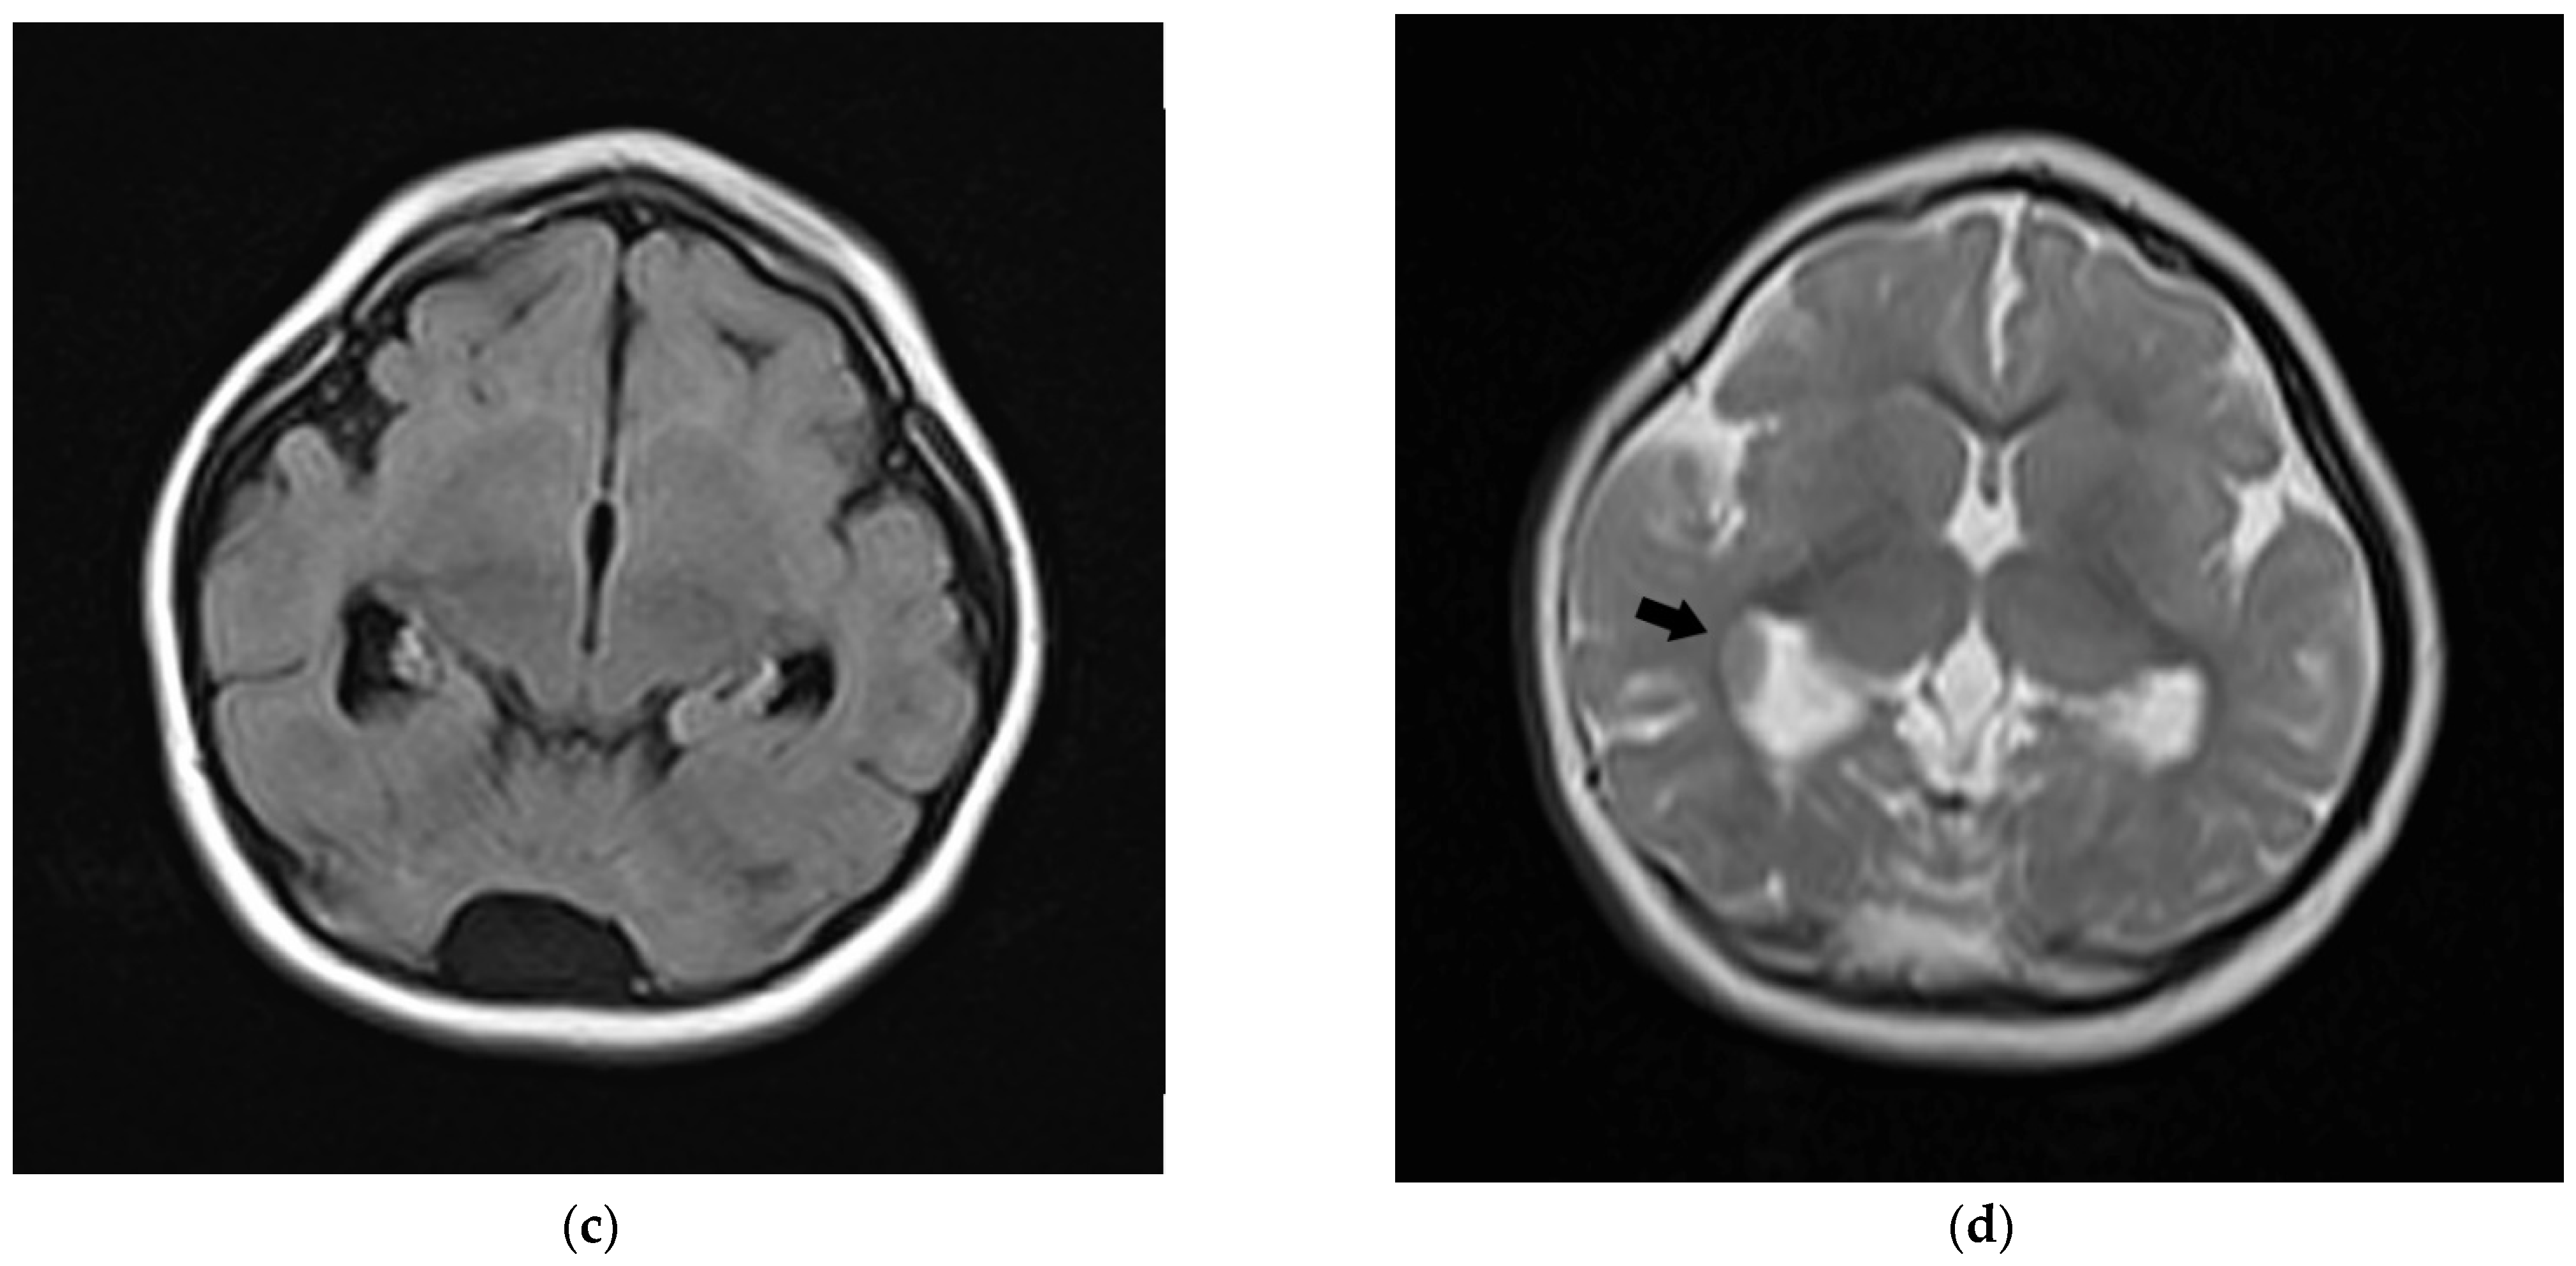

| This report | 1 | del ex 1−8 | −3.5 | −5 (10 y) | −2 | mild DD, profound ID (no language) | fronto-polar simplified gyral pattern, PNH, mild ventriculomegaly, enlarged posterior fossa | sloping forehead, highly arched eyebrow, exotropia, epicanthus, large ears; hyperactivity | Pakistani (northeast) |